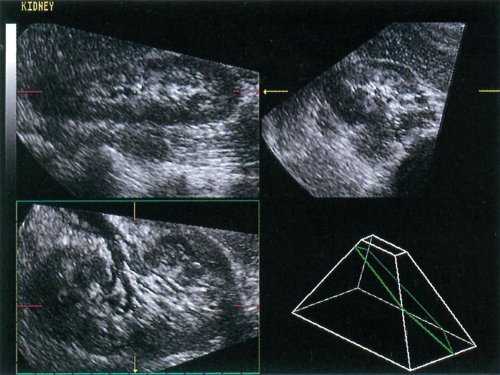

Сразу после окончания объемного сканирования (через 0,5-5 секунд) на монитор выводится изображение в трех ортогональных плоскостях (рис. 1).

Рис. 1. Продольная, поперечная и венечная плоскости изображения почки.

Каждую из этих плоскостей можно смещать в пределах объемного блока для более детального изучения или с помощью параллельного смещения (томографическое формирование срезов) или при вращении вокруг любой из трех пространственных осей. Кроме того на основании полученных данных могут быть рассчитаны трехмерные реконструкции (объемная реконструкция). В целом можно выделить три различных способа формирования изображения: